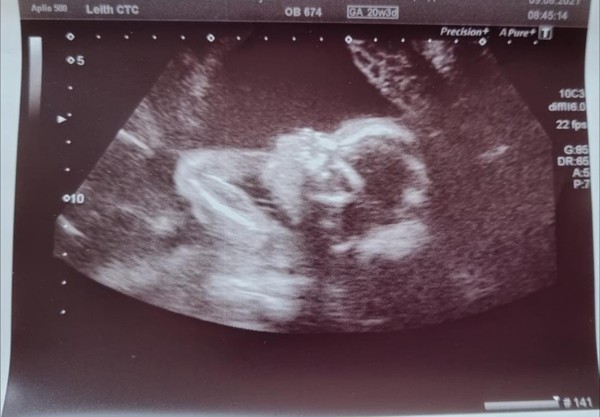

Thanks everyone for the good luck messages! ☺️ our scan today went great, all good (amazing the detail you can see). We are having a boy! 😀 Got a really cute scan photo of his wee feet!

Has everyone found out the gender then, apart from me? They don't tell you at my hospital (Larbert). The photos are rubbish too, a friend had her 12 week scan the same day as my 20 week one and her pictures was loads clearer. I wonder if it's the machine they use or something....

Excellent news on the free pram @OM82 👍 That's that problem solved 💪 You're not alone on not finding out the gender - we're waiting until delivery too 🙂 The sonographer asked if we wanted to know this morning but we said no (well, I said no... DP was in happy tears again and had lost the power of speach! 😜). I kind of want that 'reward' at the end of the pain of labour, if you see what I mean? DP's agreed that he's happy with that too (we did discuss it before we went in) 😊 On the scan pic front, our 20 week one this morning was fuzzy compared to the 12 week ones too even though it's been the same sonographer and equipment. The 12 week ones were super clear. That said, the one from this morning is clear enough to see that the poor little bugger has definitely got my over-bite! 😂 🤣

Checkout the top lip and little chin on my poor bambino @OM82! 🙈 That is truly terrifying about the nursery place situation too! 😨 I had no idea it was that bad! 😰 How on earth are first timers like us supposed to know this stuff?! I think I'm going to stick my head in the sand for a bit longer 🙉 I'm sorry your second jab has left you feeling crap 💐 I hope you start feeling better ASAP.x